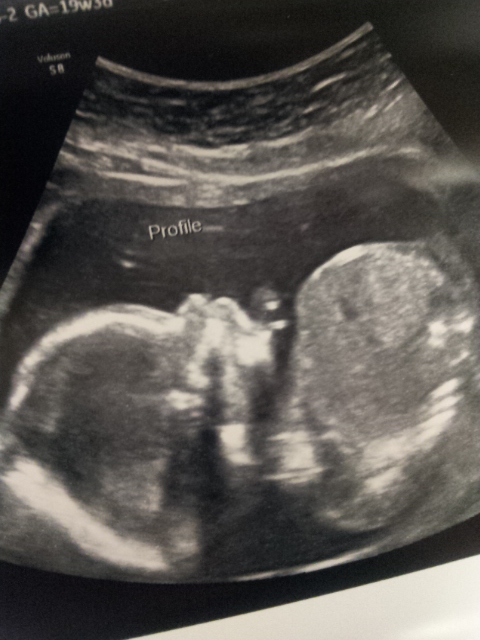

Had my anatomy scan this morning. We waited for over 40 minutes in the waiting room, and thre boys were so good. Finally got to the ultrasound room and everything looked great! All measurements match perfectly to my due date, and baby's heart rate was 147.

And we found out that we're having another boy!!!!! We are super excited!!! Name is still TBD.

Re: AW: Awesome A/S and we're having a... *** Updated with pics***